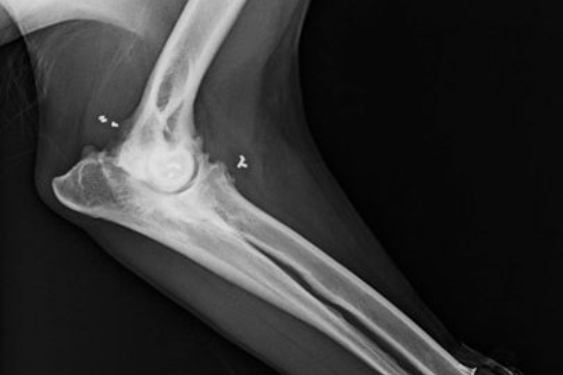

• Ellbogendysplasie

Bei der Goldimplantation werden sterile Goldstücke (24 Karat, 1-3 mm lang und 1 mm stark)) unter Inhalationsnarkose in die Nähe von Gelenken oder Schmerzpunkten injiziert. Ziel ist es, eine dauerhafte Schmerzlinderung zu erreichen, indem die Goldimplantate eine lokale Entzündungshemmung und eine Veränderung der Schmerzleitung bewirken. Hauptanliegen hierbei ist es, im Rahmen einer ganzheitlichen Versorgung des Tieres nicht einzelne Gelenke, sondern den Körper als Einheit in seiner Bewegung effizient und nachhaltig zu therapieren und Schmerzen zu lindern. Die Goldimplantate wandern nicht und stellen auch kein Hindernis für spätere Behandlungen jeglicher Art dar (Ausnahme: niederfrequente Stromformen). Es findet kein Dauerreiz statt – also handelt es sich um keine Dauerakupunktur